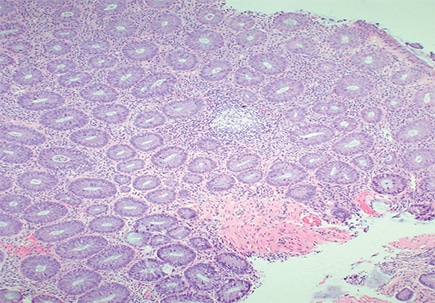

The resection specimen contained suppurative granulomatous appendicitis and active chronic enterocolitis (Figs. 1–3). Granulomatous inflammation was also noted in the endoscopic biopsies of the right colon (Fig. 4), explained Dr. Zenali, assistant professor of pathology, Department of Pathology and Laboratory Medicine, UConn Health.

Yersiniosis often involves the terminal ileum/ileocecal region and mesenteric lymph nodes; it may also affect the appendix. Suppurative and granulomatous patterns are common in Yersinia enterocolitica and in particular in Yersinia pseudotuberculosis, Dr. Zenali said. “Patients can have concurrent mesenteric lymphadenitis. The organism accesses the bowel wall through the microfold [M] cells of the Peyer’s patches, so the inflammatory reaction often initiates from the terminal ileum and ileocecal valve and can further spread to the right colon.”